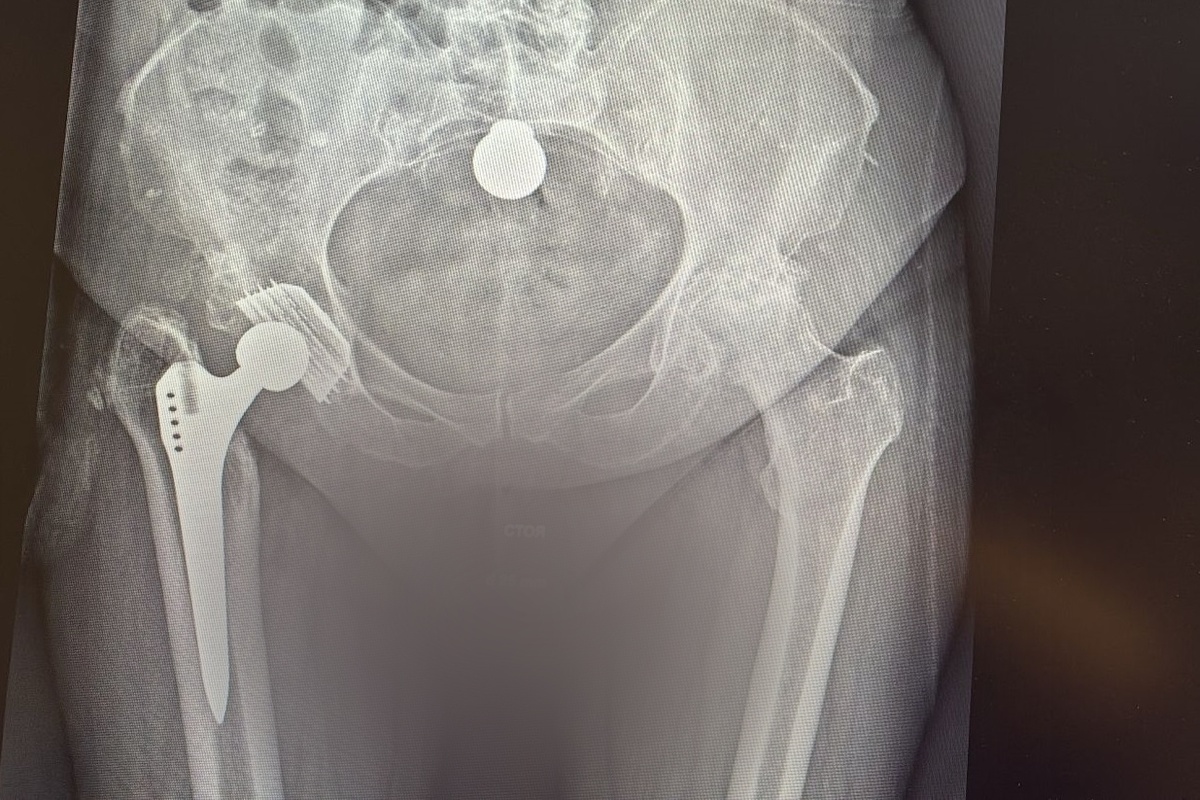

Пациентка травматолого-ортопедического отделения №2 Новосибирского НИИТО им. Я.Л. Цивьяна Минздрава России — пожилая женщина. Впервые она обратилась к врачам с жалобами на боли в правом тазобедренном суставе (ТБС) ещё в 2010 году — вследствие травмы сустав начал разрушаться, был диагностирован посттравматический коксартроз.

Хирургическое лечение заключалось в эндопротезировании сустава, и операция прошла успешно. С течением времени пациентка начала ощущать боли и ограничение движений в области левого тазобедренного сустава, и в середине 2025 года обратилась на консультацию к специалистам НИИ травматологии и ортопедии. Диагностирован идиопатический коксартроз, и хирурги-ортопеды рекомендовали выполнить эндопротезирование на левом ТБС, с реконструкцией биологической оси нижних конечностей, — на этот раз с применением робот-ассистированных технологий.

Как отмечает заведующий отделением, врач-травматолог-ортопед Максим Ефименко, при определении тактики хирургического вмешательства необходимо учитывать особенности анатомии сустава и параметры компонентов эндопротеза. В случае, когда у пациента с одной стороны установлен имплантат с определёнными параметрами, эндопротез с другой стороны должен быть имплантирован с учётом ряда нюансов.

«Цель нашей операции — оставить анатомические взаимоотношения, сохранить привычную биомеханику тазобедренного сустава так, как привычно для пациента и его походки. Принято решение применить роботизированные технологии, которые позволяют провести операцию с ювелирной точностью. Правильно установленный компонент эндопротеза позволит существенно продлить срок службы имплантата, снизить риск износа и повысить стабильность сустава.

Да, со временем изнашивание неизбежно в связи с законами трибологии, но такая точная установка позволит дольше использовать эндопротез.